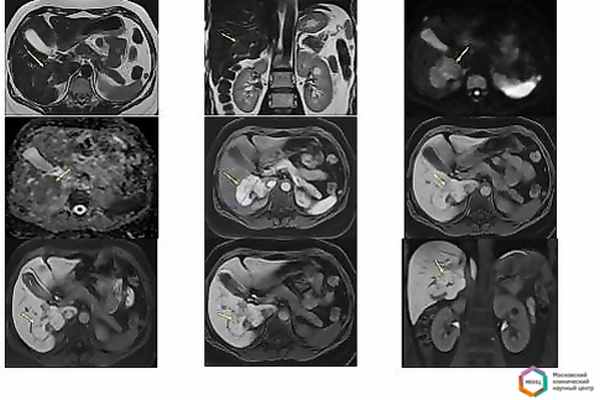

Пациентка К., 45 лет, обратилась амбулаторно в кабинет магнитно-резонансной томографии для верификации образования печени.

Анамнез: с 2013г. у больной был установлен диагноз – гемангиома печени. При узи в 2014г выявлено увеличение размеров образования до 80х60х50мм.

Лаборатнорные показатели: альфа фетопротеин 2.37 (0,5 – 5,5 МЕ/мл норма)

Показана морфологическая верификация после пункционной биопсии в онкологическом стационаре. Однако, из-за крупных размеров образования и опасности кровоизлияния в пункции больной отказано и выполнена эмболизация питающей артерии, после чего размеры образования уменьшились, а контуры деформировались.

По данным МСКТ с контрастированием – КТ картина объемного образования печени, может соответствовать фокальной нодулярной гиперплазии (дифференцировать с аденомой и раком печени).

Поскольку после эмболизации питающего сосуда и «сжатия» образования, контуры и структура деформируются, и мы ожидаем по данным МРТ, увидеть картину отличную от «классической» при фокальной нодулярной гиперплазии, единственным способом неинвазивной верификации природы опухоли является обнаружение или исключение признаков злокачественности.

Именно поэтому в кабинете МРТ пациентке предложено выполнение МРТ с гепатотропным контрастным препаратом Примовист. Несмотря на его более высокую стоимость, по сравнению с обычным контрастным препаратом, рекомендовано именно его применение для исключения наличия злокачественных клеток и подтверждения наличия здоровых гепатоцитов в структуре.

Рис 1. По данным МРТ мы визуализируем крупное образование, с неровными бугристыми контурами, активно накапливающее контрастный препарат и имеющее повышенный сигнал при диффузии и пониженный на ADC (косвенные признаки злокачественной структуры). Однако, на отсроченных гепатоспецифичных фазах контрастирования (на 10й, 20й и 30й минутах) мы видим, что образование сохраняет ту же интенсивность, что и печень т.е. в структура их идентична и представлена здоровыми гепатоцитами. В данном случае операция не показана. Пациентка отправлена домой. Рекомендовано наблюдение за ростом образования раз в год методом УЗИ

Данный случай очень показателен. Поскольку при первично правильном выборе метода обследования и контрастного препарата, позволил бы пациенту избежать многих «лишних» и неинформативных диагностических процедур и переживаний по поводу , возможно, злокачественной природы образования. А в некоторых случаях, подобная ошибка в диагностике и неясность, могли бы привезти к неоправданной травматичной операции.